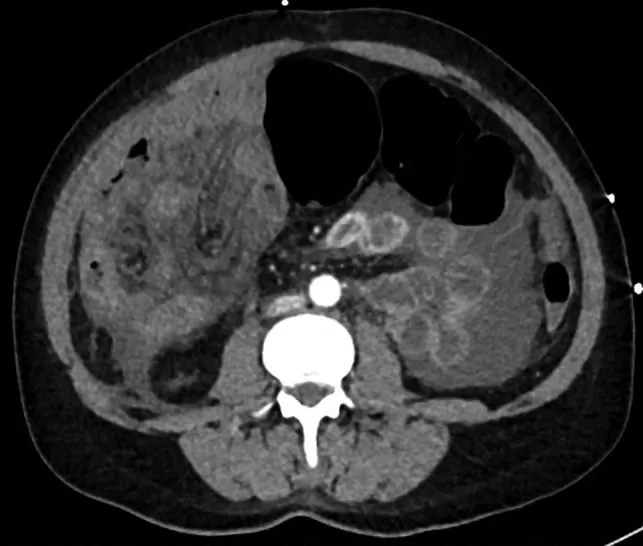

На следующее утро пациентка пожаловалась на боли в животе. Чтобы исключить перфорацию, была проведена рентгенография органов брюшной полости. Выявлен газ в петлях кишки без свободного газа в брюшной полости (рис. 1) Состояние пациентки в течение дня ухудшалось: возникла тахикардия до 134 ударов в минуту и упало давление до 67/47 мм рт. ст. При РКТ органов брюшной полости обнаружена перицекальная грыжа с петлями подвздошной кишки, расположенными по ходу правой половины ободочной кишки, с признаками ишемии (рис. 2), а также умеренное количество свободной жидкости без свободного газа (рис. 3).

Рисунок 2 [1].